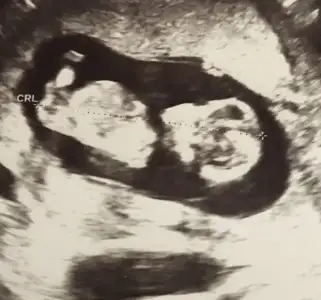

Ilk bebeginmiCanım çok teşekkürler. 3 ayı bitirmiş olacağım bir sonraki kontrolde, doktordan izin alır almaz yürüyüşteyim inşallah.

Tek sığınağım kiloyla ilişkili bir rahatsızlığım yok çok şükür ama tabii bebeğimi riske atma düşüncesi beni üzüyor. Onun için tekrar deneyeceğim :)

simsi erkek derse millete nasil soyliycem bilmiyorum